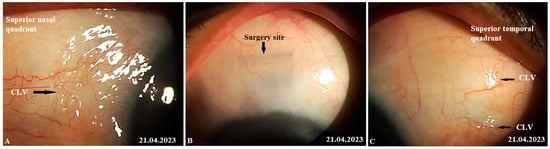

Figure 9. Slit-lamp view of the surgical site and superior quadrants in a patient’s left eye in which CLVs developed immediately after Nd:YAG laser trabeculotomy: (A) Ten minutes after Nd:YAG laser trabeculotomy, the surgical site and nearby areas are free from CLVs; some swelling at the surgical site persists. (B) Ten minutes after Nd:YAG laser trabeculotomy, another slit-lamp view of the superior temporal quadrant showing a plexus of CLVs (black arrows). (C) Thirty minutes after the procedure, slit-lamp view of the superior temporal quadrant after massaging the area with the lid margin; a well-developed plexus of CLVs can be observed far away from the surgery site. CLV = conjunctival lymphatic vessel; Nd:YAG laser = neodymium yttrium aluminum garnet laser.